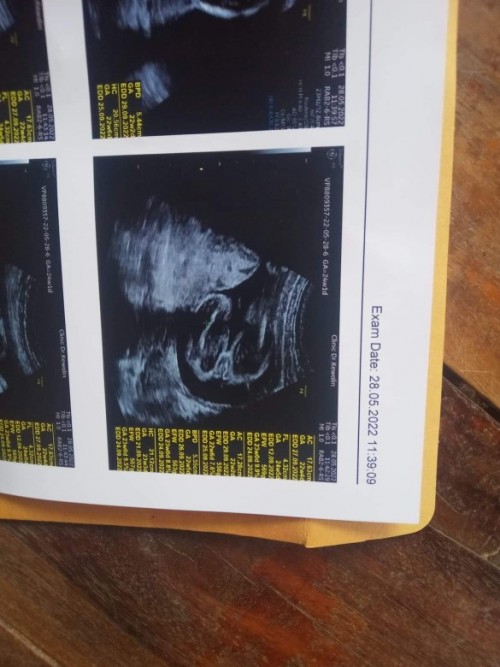

ชัดมากค่ะ เชื่อคุณหมอได้เลยค่ะคุณแม่ แหลมมาเชียว 😅

ของเราหญิงค่ะแม่ของแม่น่าจะชายค่ะ

เป็นแท่งขนาดนี้ ลูกชายแน่นอนค่ะ

โด่มาเลยแม่555

ชายจ้า

ชัดเลยค่ะ